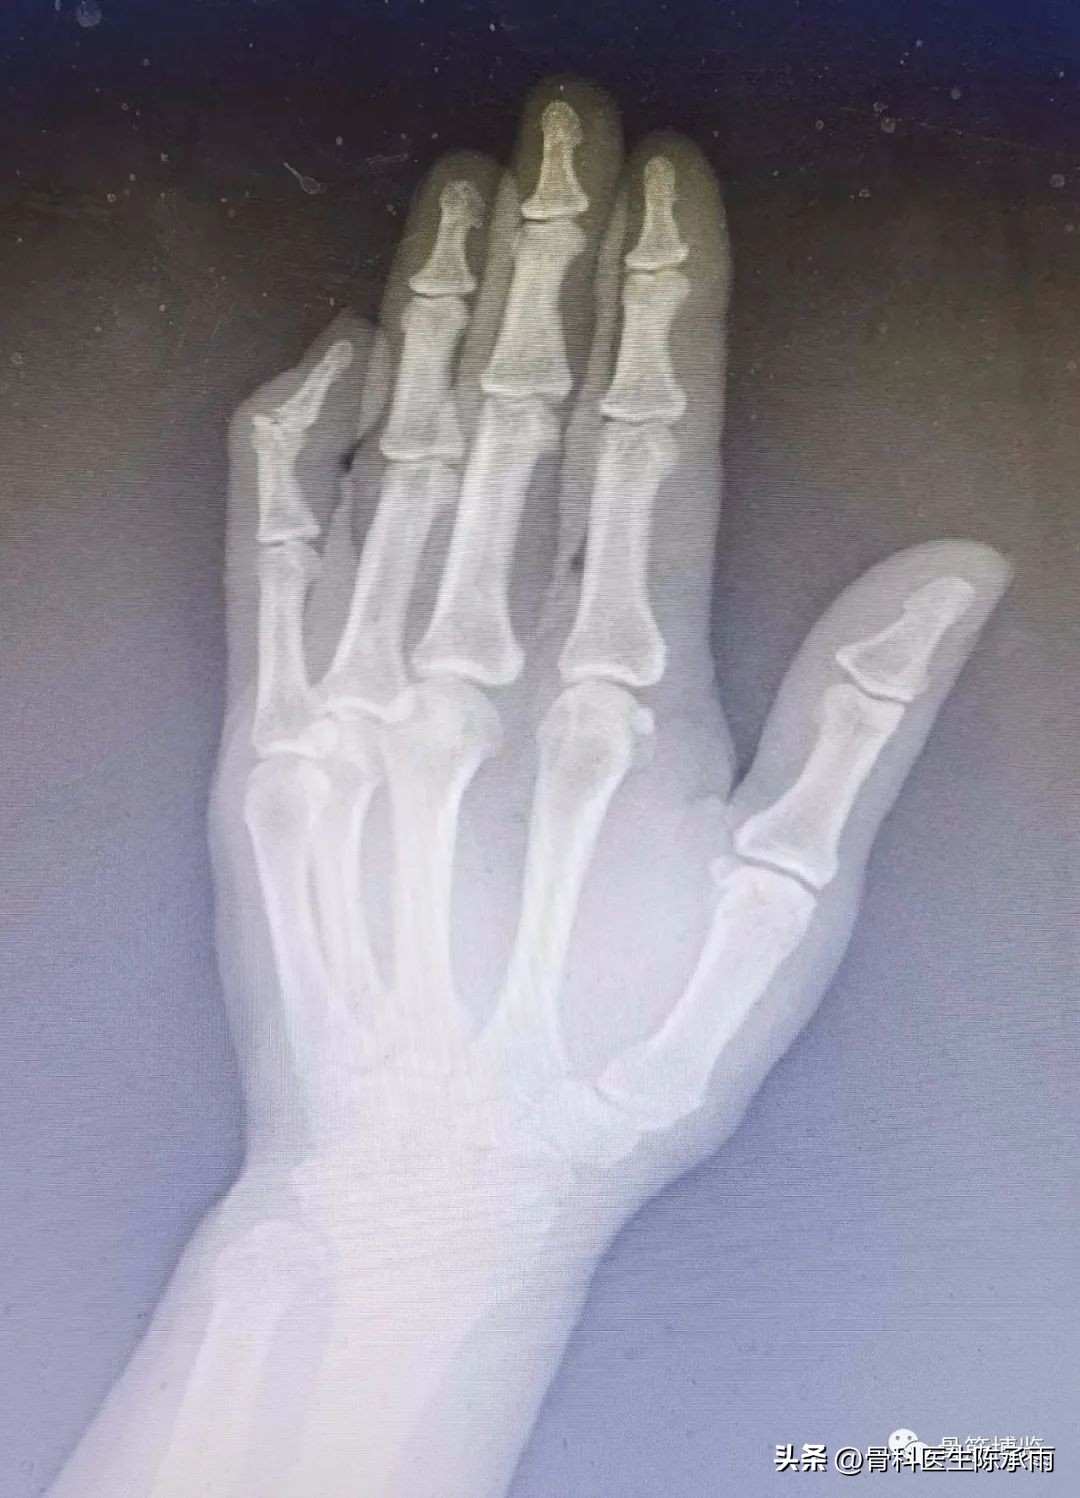

手指发生损伤后,手指最末一节不能主动伸直,被动可以伸直,手指像锤子头一样弯下来。弯曲不受影响。最末的关节背侧可以有些肿胀。

锤状指是手指伸肌腱止点处撕脱或同时伴有远节指骨背侧关节缘骨折。一般是伸直位急性屈曲力量挫伤所致,常见于小指、环指和中指,如未予治疗可能发展为鹅颈畸形和伸指装置松弛。